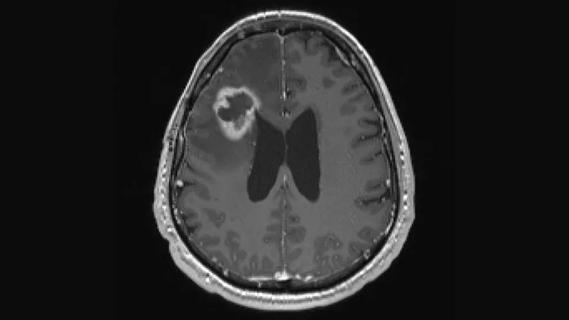

To better define these risks, his team did a retrospective chart review of 121 patients with IPH who underwent brain CT or MRI as well as cEEG monitoring at Cleveland Clinic from January 2013 to December 2014. They found that a significant share of patients with IPH and seizures on cEEG had subcortical hemorrhages, accounting for 28 percent of cases with seizures and an abnormal EEG (defined as PLEDs).